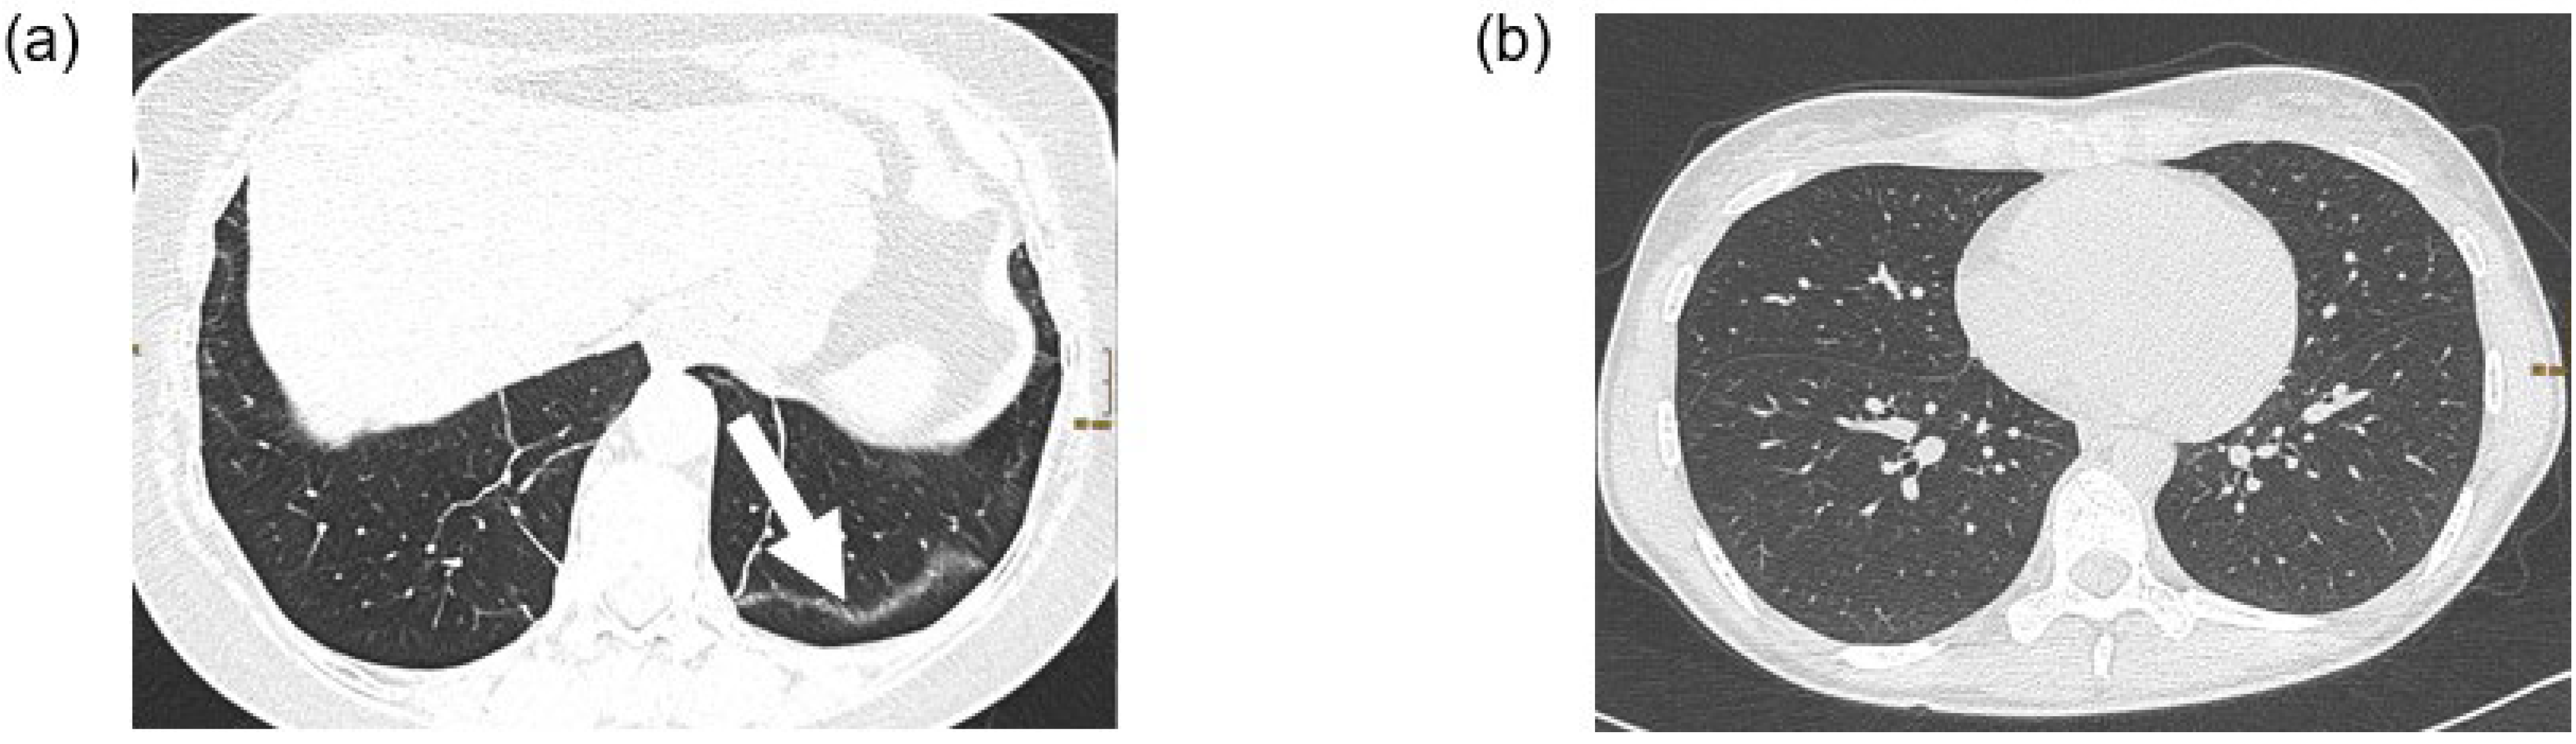

Figure 2 shows an example of a patient with possible post-COVID-19 features (subpleural bands) and a patient with a normal chest CT scan.

Figure 2. Two examples of chest CT scans. (a) CT examination in supine position of a 62 year old female patient with post-COVID-19 syndrome. The lung parenchyma shows subpleural bands (arrow) in the left lower lobe as sign of residual post-COVID changes. (b) CT examination in prone position of a 32 year old female patient with post-COVID-19 syndrome. The lung parenchyma is unremarkable.